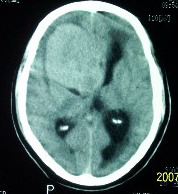

f    29岁   头闷  头晕1月余

肿瘤累及颅底前颅窝,部分层面见散在钙化,中心坏死。支持:脑膜瘤!

这么大,鞍上压迫那么厉害,梗阻也比较重没有视力及其他症状吗?从肿瘤本身表现看,支持考虑颅底脑膜瘤

肿瘤长入侧脑室,侧脑室明显扩大, 病灶边界清楚,其内可见低密度坏死区,中枢神经细胞瘤?室管膜瘤?

镰旁高密度灶,中间低密度坏死区,周围水肿较轻,支持脑膜瘤诊断,建议结合增强扫描。

右额叶底部巨大等低混杂密度肿块,边界清楚,周围水肿轻度,明显占位效应。蝶鞍扩大,部分骨质破坏。

考虑脑膜瘤,建议增强扫描进一步检查。

蝶鞍受压吸收,可以排除室管膜瘤。肿瘤最大层面不在蝶鞍可以排除垂体瘤。支持脑膜瘤